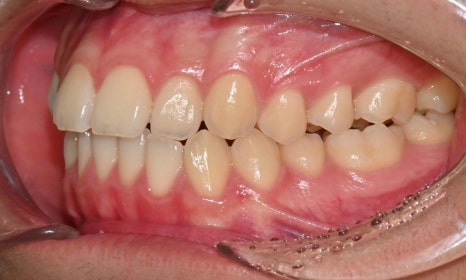

정밀 검진 결과, 하악 치열이 좌측으로 틀어져 있었고 그로 인해 위아래 치아 중심선이 일치하지 않았습니다. 아래 치열이 전체적으로 전방 위치하여 아래 입술 돌출이 더 도드라져 보이는 상태였습니다. 그리고 상악궁이 하악궁보다 좁아서 앞니 부위 일부 반대로 물리는 치아 교합도 관찰되었습니다. 특히 외상 치아의 경우, 교정력 적용시 추가적인 염증성 치근 흡수 위험이 존재하기 때문에, 치료 중 지속적인 관찰이 필수적인 상황이었습니다.

치료 시작 7개월 후 사진으로, 치아 배열 후 아래 우측에 미니스크류를 식립하여 치아 중심선을 개선하는 중으로, 교합과 치아 중심선이 많이 개선된 것을 확인할 수 있습니다.